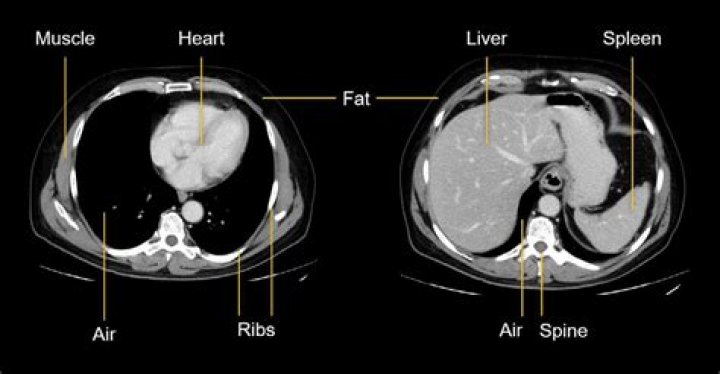

After placing your body in a tunnel-like scanner, the inside of the scanner rotates and takes multiple images from various angles. It is from these images that slices or cross-sections of the body can be created on a computer.

What organs show up on a chest CT scan?

The lungs, heart, blood vessels, airways, ribs, and lymph nodes are all examined in a chest CT (computed tomography) scan. It is possible to determine the underlying cause of chest symptoms such as cough, shortness of breath, and chest pain by using CT scans of the chest.